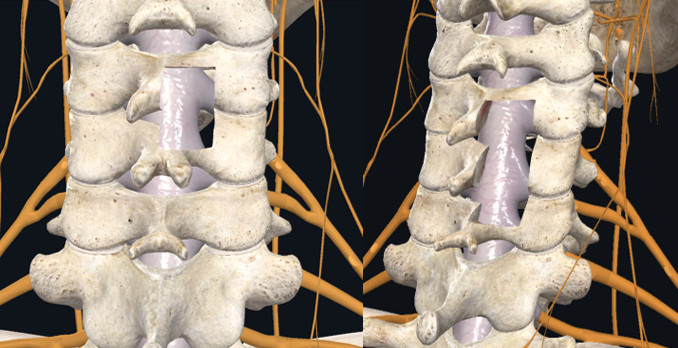

本期为大家分享荣获2019年度“精艺求菁-神经外科青年医师手术技能大赛”脊髓脊柱手术组季军的优秀病例,由解放军总医院第六医学中心张雷鸣医师带来的:脊柱内镜后路半椎板减压治疗颈椎后纵韧带骨化症,王贵怀教授、王振宇教授、车晓明教授及王劲教授点评。欢迎观看、分享。